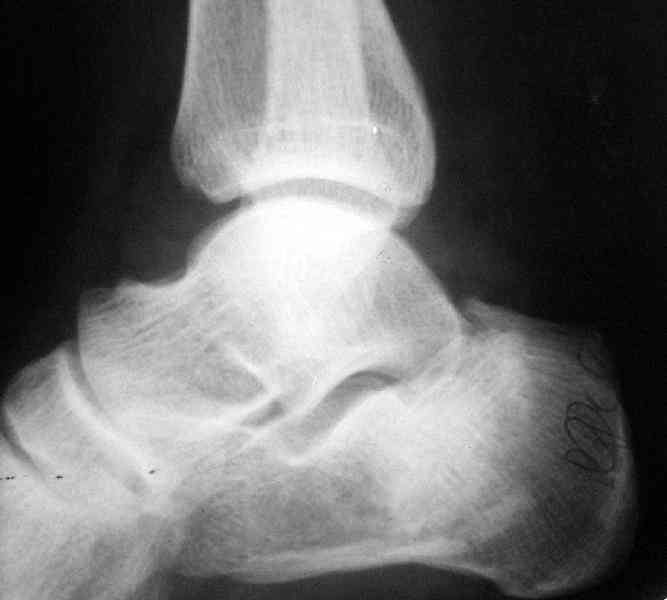

Если я правильно понял, вы хотели спросить: "Что делать с кистой, и как на этом фоне выполнять репозицию и фиксацию перелома?"

Я думаю, что для начала нужно выполнить КТ пяточной кости и определиться с границами полости. Не исключено, что отрывной перелом верхнего полюса бугра носит патологический характер (верхняя стенка кисты).

Its a comminuted one.

I would have a CT prior 2 surgery(If u have to postpone a surgery for it - I would operate without one)

Перелом безусловно внутрисуставной. Киста-не киста принципиального значения не имеет.